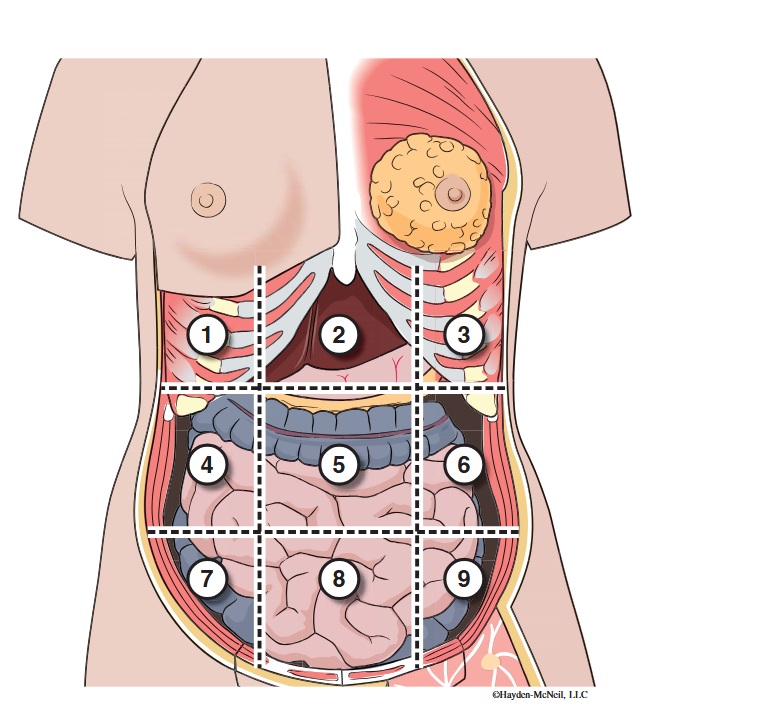

What abdominal region is labeled #1?

right hypochondriac

What abdominal region is labeled #2?

epigastric

What abdominal region is labeled #3?

left hypochondriac

What abdominal region is labeled #4?

right lumbar

What abdominal region is labeled #5?

umbilical

What abdominal region is labeled #6?

left lumbar

What abdominal region is labeled #7?

right iliac/ inguinal

What abdominal region is labeled #8?

hypogastric

What abdominal region is labeled #9?

left illiac/ inguinal

What organs are apart of the right hypochrondriac region?

right lobe of liver, gallbladder, right adrenal gland

What organs are apart of the epigastric region?

pyloric end of stomach, duodenum, pancreas

What organs are apart of the left hypochondriac region?

stomach, spleen, left adrenal gland

What organs are apart of the right lumbar region?

ascending colon, right kidney, portion of small intestine

What organs are apart of the umbilical region?

omentum, mesentery, small intestine

What organs are apart of the left lumbar region?

descending colon, left kidney, portion of the small intestine

What organs are apart of the right iliac/ inguinal region?

cecum of large intestines, appendix, right ovary

What organs are apart of the hypogastric region?

ileum, bladder, uterus

What organs are apart of the left iliac/ inguinal region?

sigmoid colon, left ureter, left ovary